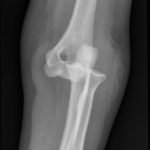

Elbow dislocations are classified by the position of the radio-ulnar joint relative to the humerus.1 Images 1, 2, and 3 show a left posterior elbow dislocation; the radius and ulna are displaced posteriorly with respect to the distal humerus. The lateral view of the elbow most clearly shows this: trochlear notch of the ulna is empty and displaced posteriorly relative to the trochlea. There is no associated fracture. Images 4 and 5 show the elbow status-post reduction, demonstrating proper alignment of the distal humerus with the radius and ulna.